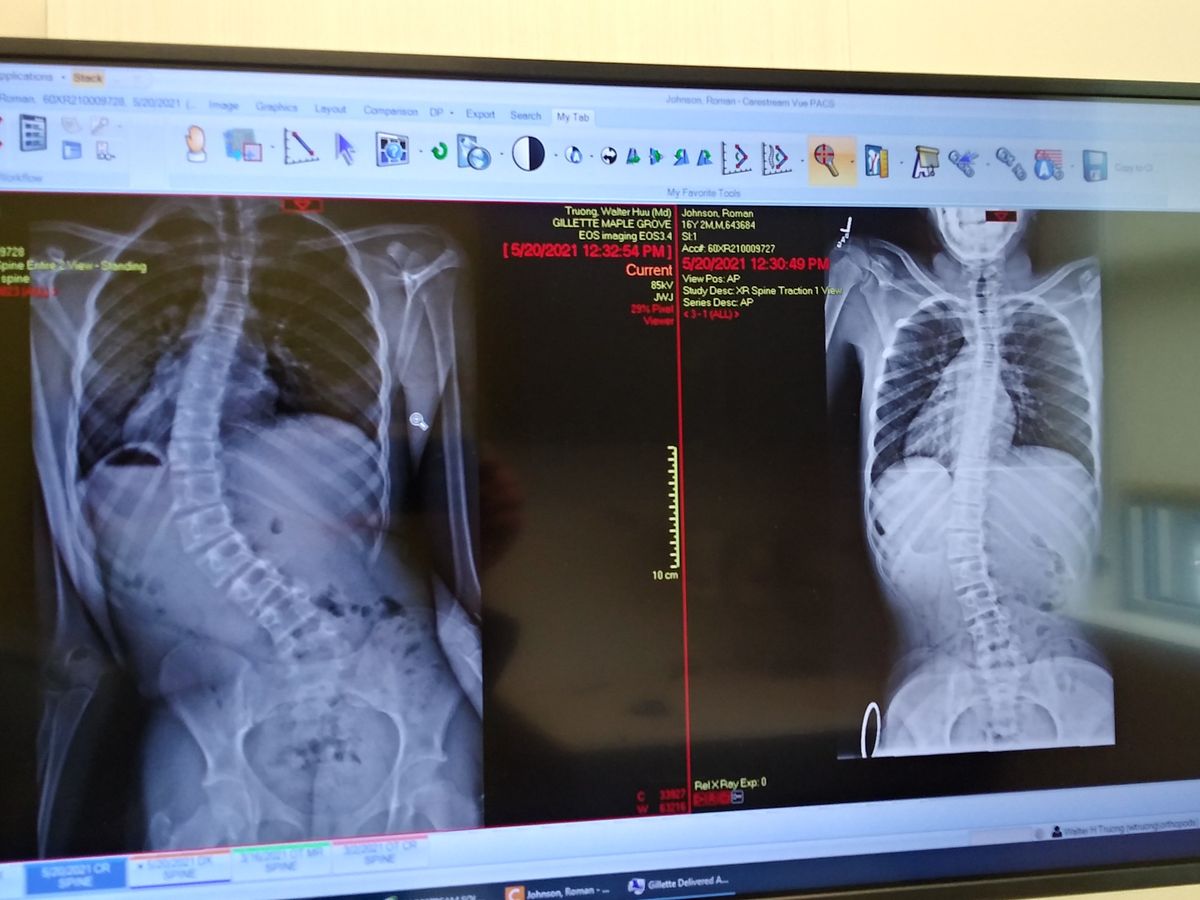

Proud single mother who has an amazing 16 year old son that was recently diagnosed with Scoliosis and is needs immediate Idiopathic Surgery before organ failure onsets. We have an amazing surgeon at Gillette's Children's Hospital and spinal surgery is taking place on June 14th 2021. There will be a 3-4 day stay at the hospital and 4 weeks post surgery he will have to have 4-6 weeks of rehabilitation therapy 2 times a week. They are inserting a rod from right below his neck to right above his pelvic bone. Many prayers and well wishes are so much appreciated! Thank you in advance for anything you are able to contribute, I am very modest in my ask and will not know fully out of pocket it will end up being. An important message is he .. Is going to have an Iron Man back. (His fav Marvel Hero)